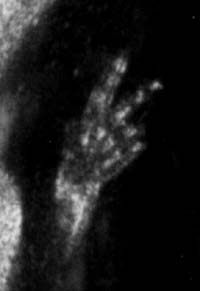

20. týden: ruka plodu ve 20. týdnu - je mozno vizualizovat vsechny clanky prstu (poskytla gyn.-por. klinika FN Motol, Dr.Hrehorčák)